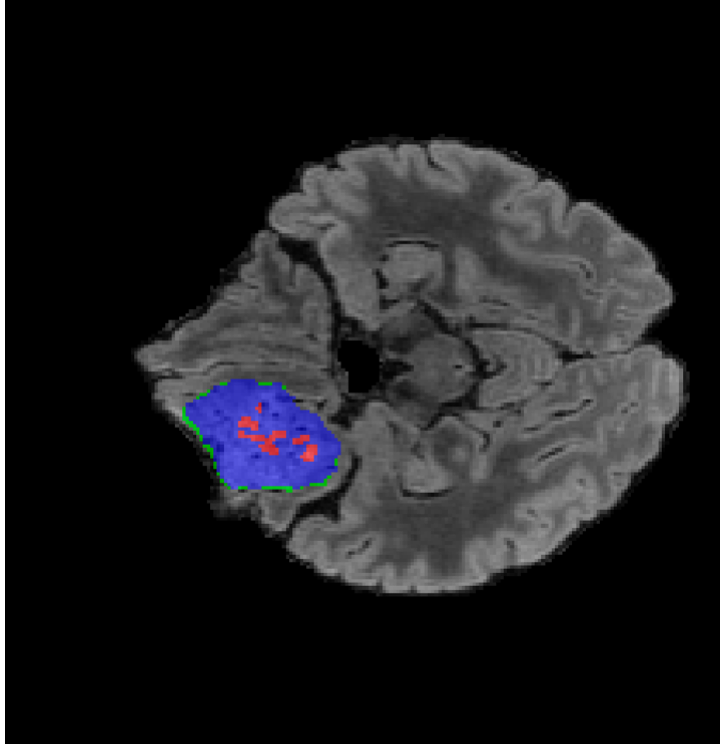

Tumour Information Preservation. For the brain tumor segmentation, we use a Swin UNETR model[27, 70], trained with random rotation, and intensity as data augmentation. In Figure 5, we highlight the tumor profiles of the generated MRIs compared to the ground truth tumour profile. In the test set with human ground-truth annotations (), the real MRI Dice score is 85.15 while the generated MRIs from a single slice have a dice score of 83.09. This shows how the generated MRIs indeed preserve the tumor information and can act as an affordable and informative pseudo-MRI, before conducting an actual costly MRI examination in hospitals.

B.4 Tumour Information Preservation

On the test set with human ground-truth annotations (), the brain volumes generated from single slice input preserve the volume of the different tumour components (paired t-test, for all 3 classes) (see Table 3). The real MRI Dice scores are put for reference to our generated MRIs. X-Diffusion outperforms baselines TPDM [36] and ScoreMRI [18] in tumour preservation (see Table 3 and Figure 12). We ran experiments comparing the tumour segmentation Dice Score varying X-Diffusion configurations. The multi-slice input X-Diffusion achieves a marginally better Dice Score than the single-slice input model (83.47 83.09). We also ran experiments with slice input used for volume reconstruction intersecting or not with tumour. We observe on average a drop of 6% Dice Score (see Table 3). Further away from the tumour the input slice for volume reconstruction is selected, and we observe a linear decrease in tumour segmentation Dice Score with the lowest value of 77.21 Dice Score (see Figure 15).

This shows how the generated MRIs indeed preserve the tumour information and can act as an affordable and informative pseudo-MRI, before conducting an actual costly MRI examination in hospitals. Given that our model has been trained on brain scans all with tumours, we expect to see hallucinations of tumours in healthy scans. We report two cases of failure of our model in Figure 16. Hallucinations of tumours on healthy samples represent 2% of the test set.

| Test Dice Score | |||||

|---|---|---|---|---|---|

| X-Diffusion Generated MRIs | ET | WT | TC | Average Dice | 3D PSNR(dB) |

| single slice | 75.48 | 89.24 | 84.57 | 83.09 | 35.81 |

| multi-slice | 75.82 | 89.56 | 85.04 | 83.47 | 36.13 |

| multi-slice (only-tumour) | 76.12 | 90.04 | 85.87 | 84.01 | 36.98 |

| multi-slice (no-tumour) | 70.14 | 84.29 | 81.65 | 78.69 | 33.24 |

| Real | 76.47 | 91.13 | 86.24 | 85.15 | N/A |